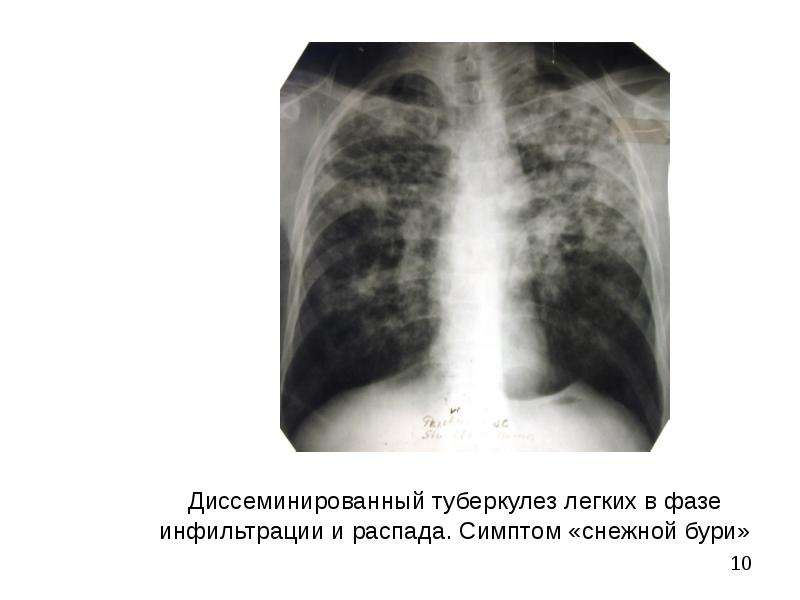

Симптомы и лечение инфильтративного туберкулеза легких

Раздел: Снимки-откровения